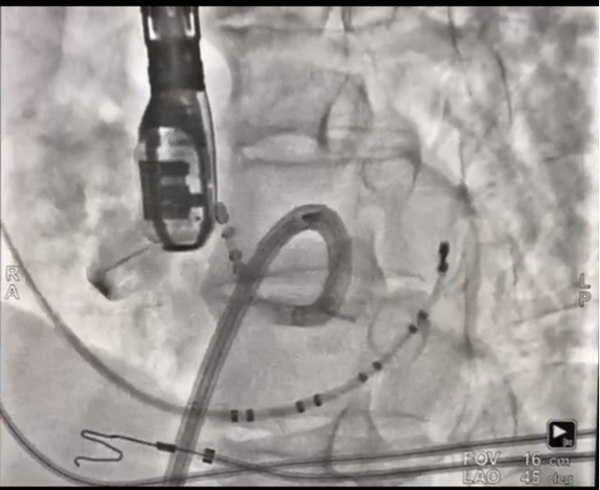

图片1_副本.png

主动脉瓣上激动标测

图片2_副本.png

主动脉瓣下激动标测和射频消融